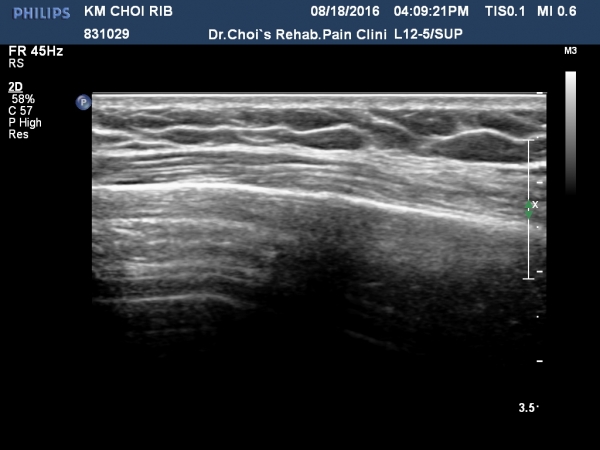

ÃÊÁø ½Ã °¥ºñ»À ÃÊÀ½ÆÄ°Ë»ç¿¡¼­ ÇÇÁú°ñ ¤·³à¼Ó¼º ¼Ò½ÇÀº º¸ÁöÁö ¾ÊÀ¸³ª

±æºñ»À Ç¥Ãþ¿¡ ±¹¼ÒÀûÀÎ ¿¬ºÎÁ¶Á÷ ºÎÁ¾ÀÌ °üÂûµÈ´Ù(»çÁø 1, 2, 3, 4).